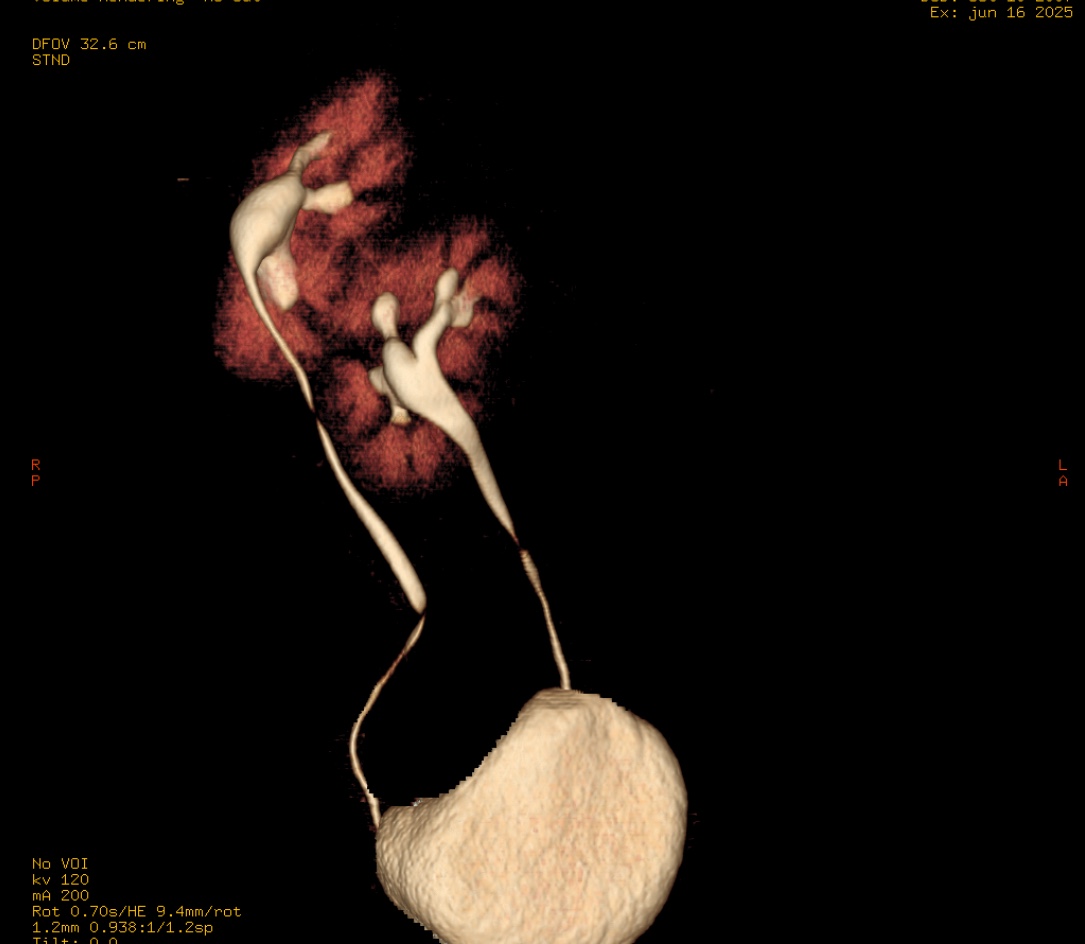

Caso #1: Ectopía Renal Cruzada Fusionada

Paciente femenina en la que se identificó ausencia de riñón izquierdo en fosa renal, con fusión renal en flanco derecho. Las reconstrucciones 3D y cortes axiales confirman una ectopía renal cruzada tipo A con malrotación de ambos riñones. Cada uréter conserva su trayecto anatómico hacia su meato correspondiente en vejiga.

Corte axial TC Reconstrucción 3D 1 Reconstrucción 3D 2 Plano sagital VR uréteres